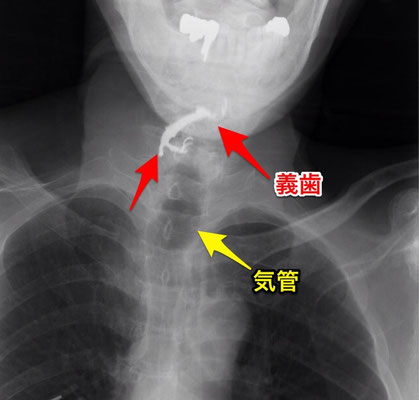

上のものに似ていますが、足の部分がかなり曲がっており、粘膜への食い込みが強く、口腔からの摘出は困難でした。

そのため、外切開を行い、食道の上の方の粘膜に切開を入れて摘出されました。